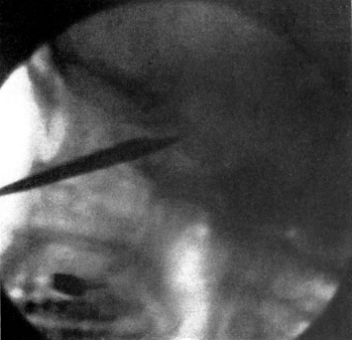

| 267. | Skiagram showing an Angular Tracheotomy Tube in the Trachea | 518 |

| 268. | Anatomy of the Larynx and Trachea and the Position of Incisions for the Operations in this Region | 525 |